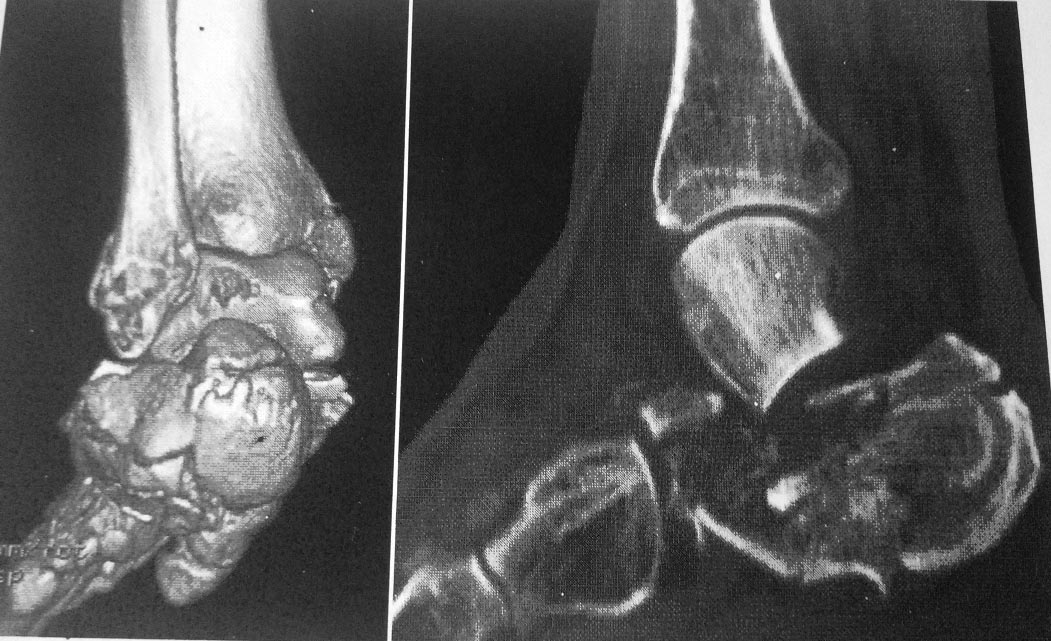

Дополнительно дооперационная СКт

Р

2

3